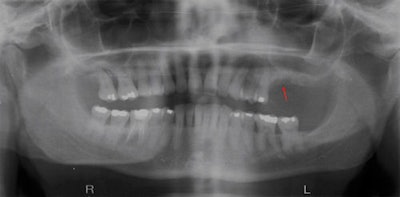

"Despite being a pathologic condition of bone, there are no established diagnostic radiographic criteria for BONJ," Dr. Treister and colleagues noted. "Several studies have reported various radiographic findings from panoramic films and computed tomography that include sclerosis, cortical surface irregularities, [and] persistent extraction sockets. However, the frequency and consistency of these findings, and the relationship between clinical and radiographic signs, remain unclear."

They reviewed the records of 39 cancer patients who had been diagnosed with BONJ and examined using panoramic radiography. After dividing the arches into sextants and evaluating them for signs of sclerosis, surface irregularity, sockets, fragmentation, and lysis, they found that 62 of the 234 sextants were abnormal by clinical criteria, and 61 demonstrated at least one radiographic abnormality. In addition, the total number of radiographic signs per patient increased with the BONJ stage.

"This represents the first study specifically evaluating the panoramic radiograph features of BONJ and their relationship with both the location and extent of clinical findings," the authors concluded. "Our data demonstrated that radiographic findings of sclerosis, surface irregularity, and persistent sockets correlate significantly with clinical sites of BONJ."

| Image courtesy of Nathaniel Treister, D.D.S. |